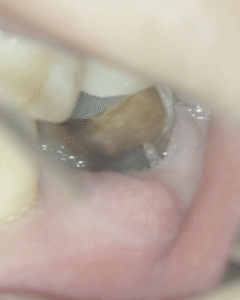

初診時にあった歯肉の腫脹(↓)は消失していた。